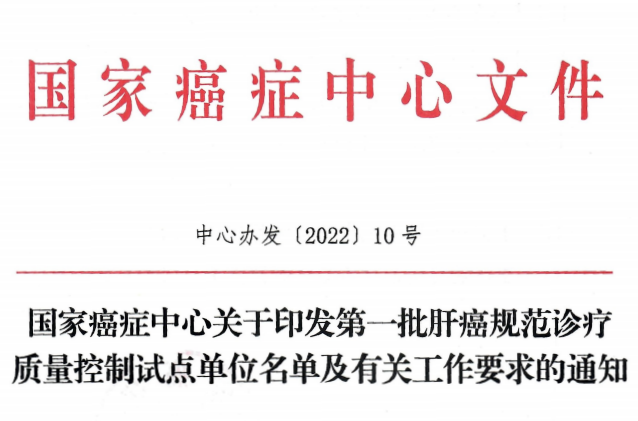

喜报 | 柳州市工人医院成为全国首批肝癌规范诊疗质量控制中心桂中区域唯一试点单位

近日,国家癌症中心发布了《关于印发第一批肝癌规范诊疗质量控制试点中心名单及有关工作要求的通知》,国家癌症中心、国家肿瘤质控中心肝癌质控专家委员会在全国遴选出第一批肝癌规范诊疗质量控制试点单位(含试点筹建),我院凭借强劲综合学科实力、规范化的诊疗技术、先进的诊疗设备等优势条件通过了层层筛选,获批全国第一批肝癌规范诊疗质量控制试点单位,成为桂中区域唯一的入选医院。

据悉,肝癌规范诊疗质量控制试点单位(含试点筹建)目前广西获批仅6家,这是我院目前继乳腺癌、卵巢癌规范诊疗质量控制试点单位后又新增一个试点病种,是我院肝癌综合诊治实力和学术地位获得国家癌症中心、国家肿瘤质控中心等国家层面肯定的体现,更是对我院肿瘤规范化诊疗整体实力的肯定。